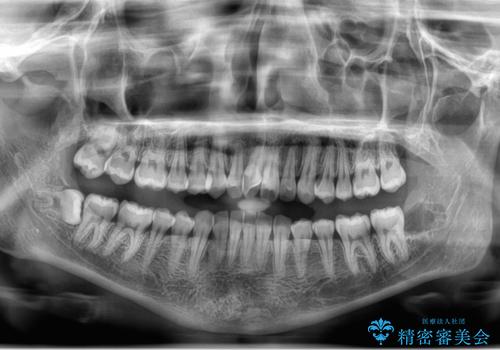

左の親知らず抜歯したい。

- 左上下親知らず抜きたいとの事で来院。

レントゲン、CTを撮影し安全を考慮して抜歯術を行いました。

抜歯後、1週間後に抜糸を行う必要があります。

無事に親知らず抜歯ができました。

次回反対側の親知らずを抜歯するか検討中です。